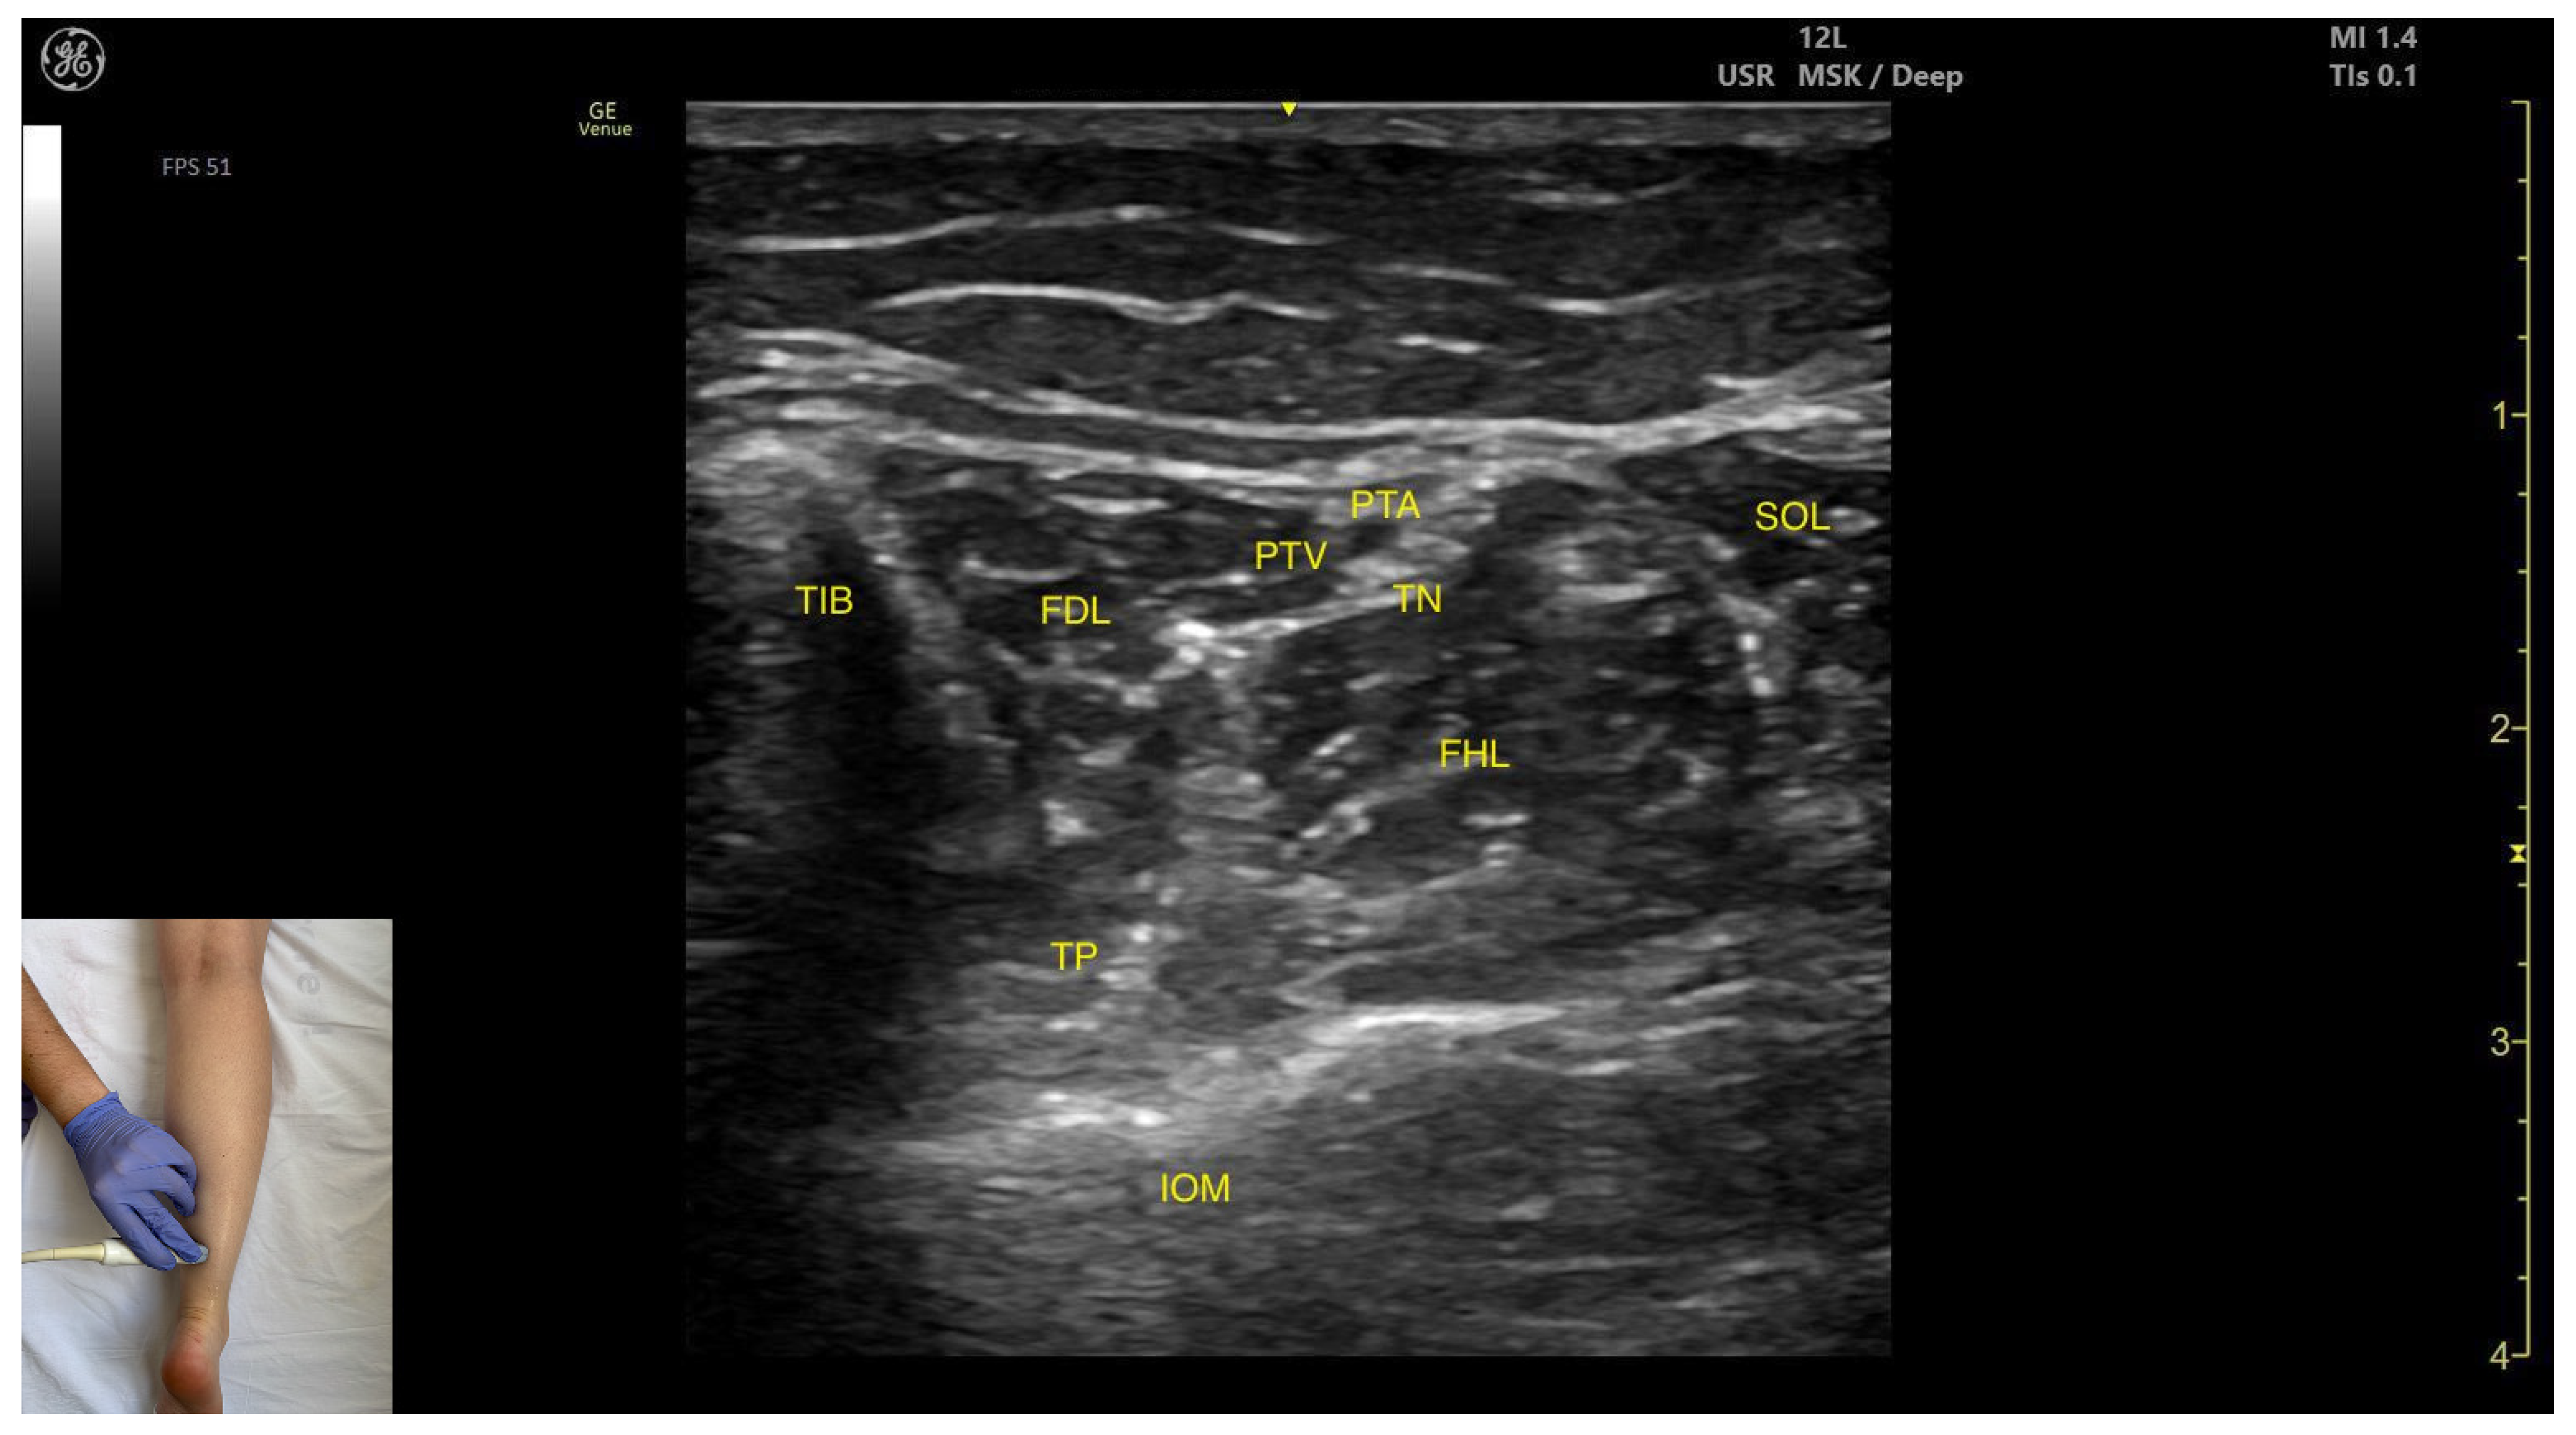

Ultrasound Identification

Key Ultrasound Landmarks

- Muscle position: The tibialis posterior is the deepest muscle in the posterior compartment of the leg. It is bordered superficially and medially by the flexor digitorum longus and superficially and laterally by the flexor hallucis longus. The interosseous membrane lies deep to the TP.

- Neurovascular bundle: Within the intermuscular fascial plane between the flexor digitorum longus, flexor hallucis longus, and soleus, the tibial nerve, posterior tibial artery, and posterior tibial vein are situated.

- External fascia: The TP does not have a well-defined fascia that separates it from flexor digitorum longus and flexor hallucis longus, during BoNT-A injection.

- Dynamic evaluation: Muscle contraction becomes evident during ankle inversion and plantar flexion at the ankle joint.

| Tibialis Posterior (medial window) | Distal third of the leg, in the medial portion | Flexor digitorum longus (superficial and medial), flexor hallucis longus (superficial and lateral); tibial nerve, posterior tibial artery, and posterior tibial vein (superficial); interosseous membrane (deep) | Transverse scan on the distal third of the leg | Avoid neurovascular injury |